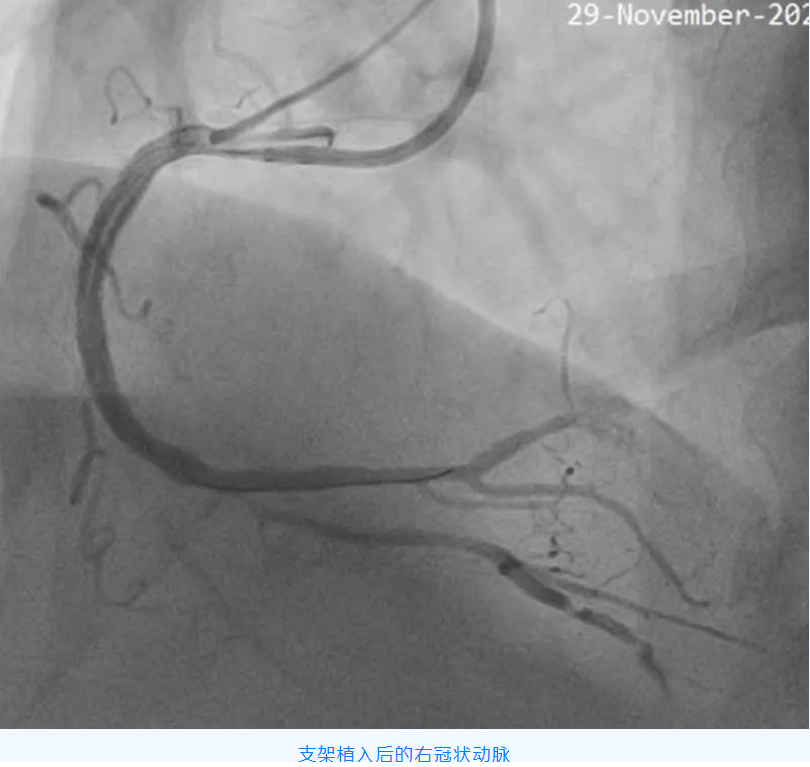

该例CTO 的成功开通,标志着星城院区心血管内科诊疗水平又有了新的突破。

冠状动脉慢性完全闭塞病变(CTO),即冠状动脉血管腔完全闭塞,且持续闭塞的时间大于 3 个月的病变。对于病人而言,成功开通 CTO 可以延长生命、改善心脏功能、增加心肌电活动稳定性,减少心律失常事件,而且还可以增加以后可能出现的冠状动脉闭塞事件耐受性及提高生活质量,越是年轻患者,开通 CTO 获益越大。

但该手术难度大、成功率低、并发症、再狭窄、再闭塞发生率高,被公认为是冠状动脉介入治疗的天花板。CTO 病变的开通成功率已成为评价医院心血管内科介入治疗水平高低的一个主要指标。